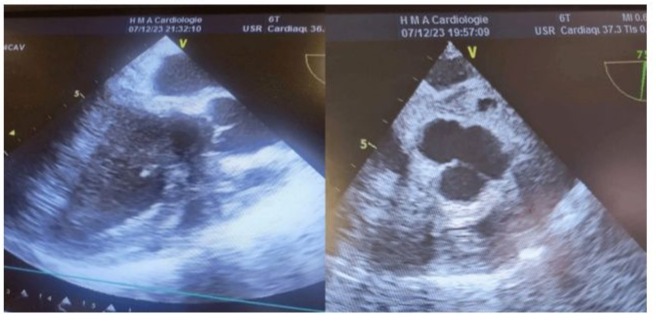

64-year-old female, with medical history of hypertension, hyperlipidemia, symptomatic mitral insufficiency presented initially with a history of repetitive episodes of acute cardiac insufficiency, worsening dyspnea on exertion, orthopnea, paroxysmal nocturnal dyspnea. Despite optimization of medical therapy with sacubitril/valsartan, spironolactone, dapagliflozin, high-dose furosemide, bisoprolol, her symptoms continued to deteriorate. In her hospitalization in cardiology, the physical examination revealed signs of congestive heart failure, including elevated jugular venous pressure, bibasilar crackles, and a pansystolic murmur loudest at the apex radiating to the axilla. Transthoracic Echocardiography (TTE): Showed severe mitral regurgitation with a flail posterior leaflet, left ventricular dysfunction with an ejection fraction of 50%, tele-systolic diameter at 44mm, dilated left atrium and ventricle, and pulmonary hypertension with an estimated systolic pulmonary artery pressure of 60 mmHg. Transesophageal Echocardiography (TEE) has confirmed TTE findings and provided detailed assessment of the mitral valve pathology, including the mechanism and severity of regurgitation, as well as assessment of the tricuspid valve and right ventricular function. Given the severity of her symptoms and the progressive nature of her disease despite optimal medical therapy, she was scheduled for surgical intervention 3 months later after stabilization and complete decongestion with the addition of higher doses of furosemide. The plan involved mechanical mitral valve replacement given that mitral valve repair was deemed unfeasible based on the TEE data and the surgical team's experience and tricuspid annuloplasty to address the valvular pathology and alleviate symptoms of heart failure. The patient underwent cardiac surgery via median sternotomy with cardiopulmonary bypass. Mechanical mitral valve replacement (size 29) and tricuspid annuloplasty using a 32-mm semi-rigid annuloplasty ring were performed. TEE provided detailed intraoperative assessment of the mitral and tricuspid valves, confirming the severity of regurgitation (Figure 1) (video 1), mechanism of valvular dysfunction, and the need for surgical intervention. It also allowed for real-time monitoring of cardiac function and assessment of the adequacy of the surgical repair (Figure 2,3) showing a reduction in sub aortic velocity-time integrals (VTI), indicative of left ventricular dysfunction and pulmonary hypertension through the analysis of the pulmonary regurgitation velocity. With a cross-clamp time of 60 minutes and a cardiopulmonary bypass (CPB) duration of 120 minutes however, the weaning from cardiopulmonary bypass was complex, requiring central extracorporeal membrane oxygenation (ECMO) support. Progressive doses of inotropic support including epinephrine Corotrope, norephedrine, and inhaled nitric oxide were administered due to persistent hemodynamic instability with evident signs of pulmonary hypertension including a hypokinetic and dilated right ventricle, paradoxical septum, significant pulmonary regurgitation with elevated mean pulmonary artery pressure (MPAP), systolic pulmonary artery pressure (SPAP), and diastolic pulmonary artery pressure (DPAP), despite high doses of inotropes and pulmonary vasodilators. The left ventricular function was clearly impaired with a hypokinetic left ventricle, which dilated after a few minutes of complete cessation of cardiopulmonary bypass support. Due to the inability to wean off cardiopulmonary bypass (CPB), And after verification via intraoperative transesophageal echocardiography (TEE) of the proper functioning of the mechanical valve (video 2,3,4), central ECMO was implemented with arterial cannulation at the left ventricular apex and venous atrial cannulation, aiming for bridge to recovery and to prevent recurrent pulmonary edema episodes on peripheral ECMO, given the high filling pressures estimated by deceleration time and the E/Vp ratio and the falling ETT has shown an absence of holosystolic aortic valve opening under veno-arterial ECMO after failure to wean from cardiopulmonary bypass, indicating severe ventricular dysfunction and the non-contribution of the heart to the cardiac output generated by mechanical circulatory support associated to proper function of the Saint-Jude-Medical bileaflet valve with a low mean transvalvular gradient, indicative of postoperative left ventricular dysfunction. (Figure 4,5)Unfortunately, the patient developed significant bleeding, the advanced laboratory tests, which took time to arrive because we do not have localized laboratory devices to guide initial therapeutic strategies, a massive transfusion of platelets, fresh frozen plasma, packed red blood cells and fibrinogen concentrates has been performed, prothrombin complex concentrates were not available. Given the hemostatic disorders with laboratory evidence of hypofibrinogenemia and thrombocytopenia, suggestive of coagulopathy and consumptive coagulopathy secondary to surgical trauma and cardiopulmonary bypass, and the need for a reoperation was not taken, the ECMO pump flow continued to decline despite increasing, due to venous line collapse following a decrease in volume (video 5,6). Despite aggressive resuscitative efforts, she succumbed to complications and expired 24 hours after surgery.

Figure 4: Midesophageal long-axis view at 120° (Left) and high esophageal view at 0° (Right) in TEE after native mitral valve replacement under PC-ECLS Showing an absence of holosystolic aortic valve opening under veno-arterial ECMO after failure to wean from cardiopulmonary bypass, indicating severe ventricular dysfunction and the non-contribution of the heart to the cardiac output generated by mechanical circulatory support.

Figure 5: TEE after native mitral valve replacement with a mechanical valve, showing proper function of the Saint-Jude-Medical bileaflet valve with a low mean transvalvular gradient, indicative of postoperative left ventricular dysfunction.